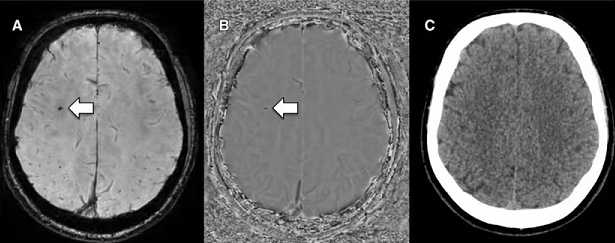

上面颅脑三幅图(MRI幅度图、MRI相位图、CT图),白箭头所指右侧额

叶斑点状黑点(专业术语:低信号)就是微出血灶,但CT未见显示,因此颅脑微出血灶检测千万不要做CT检查。